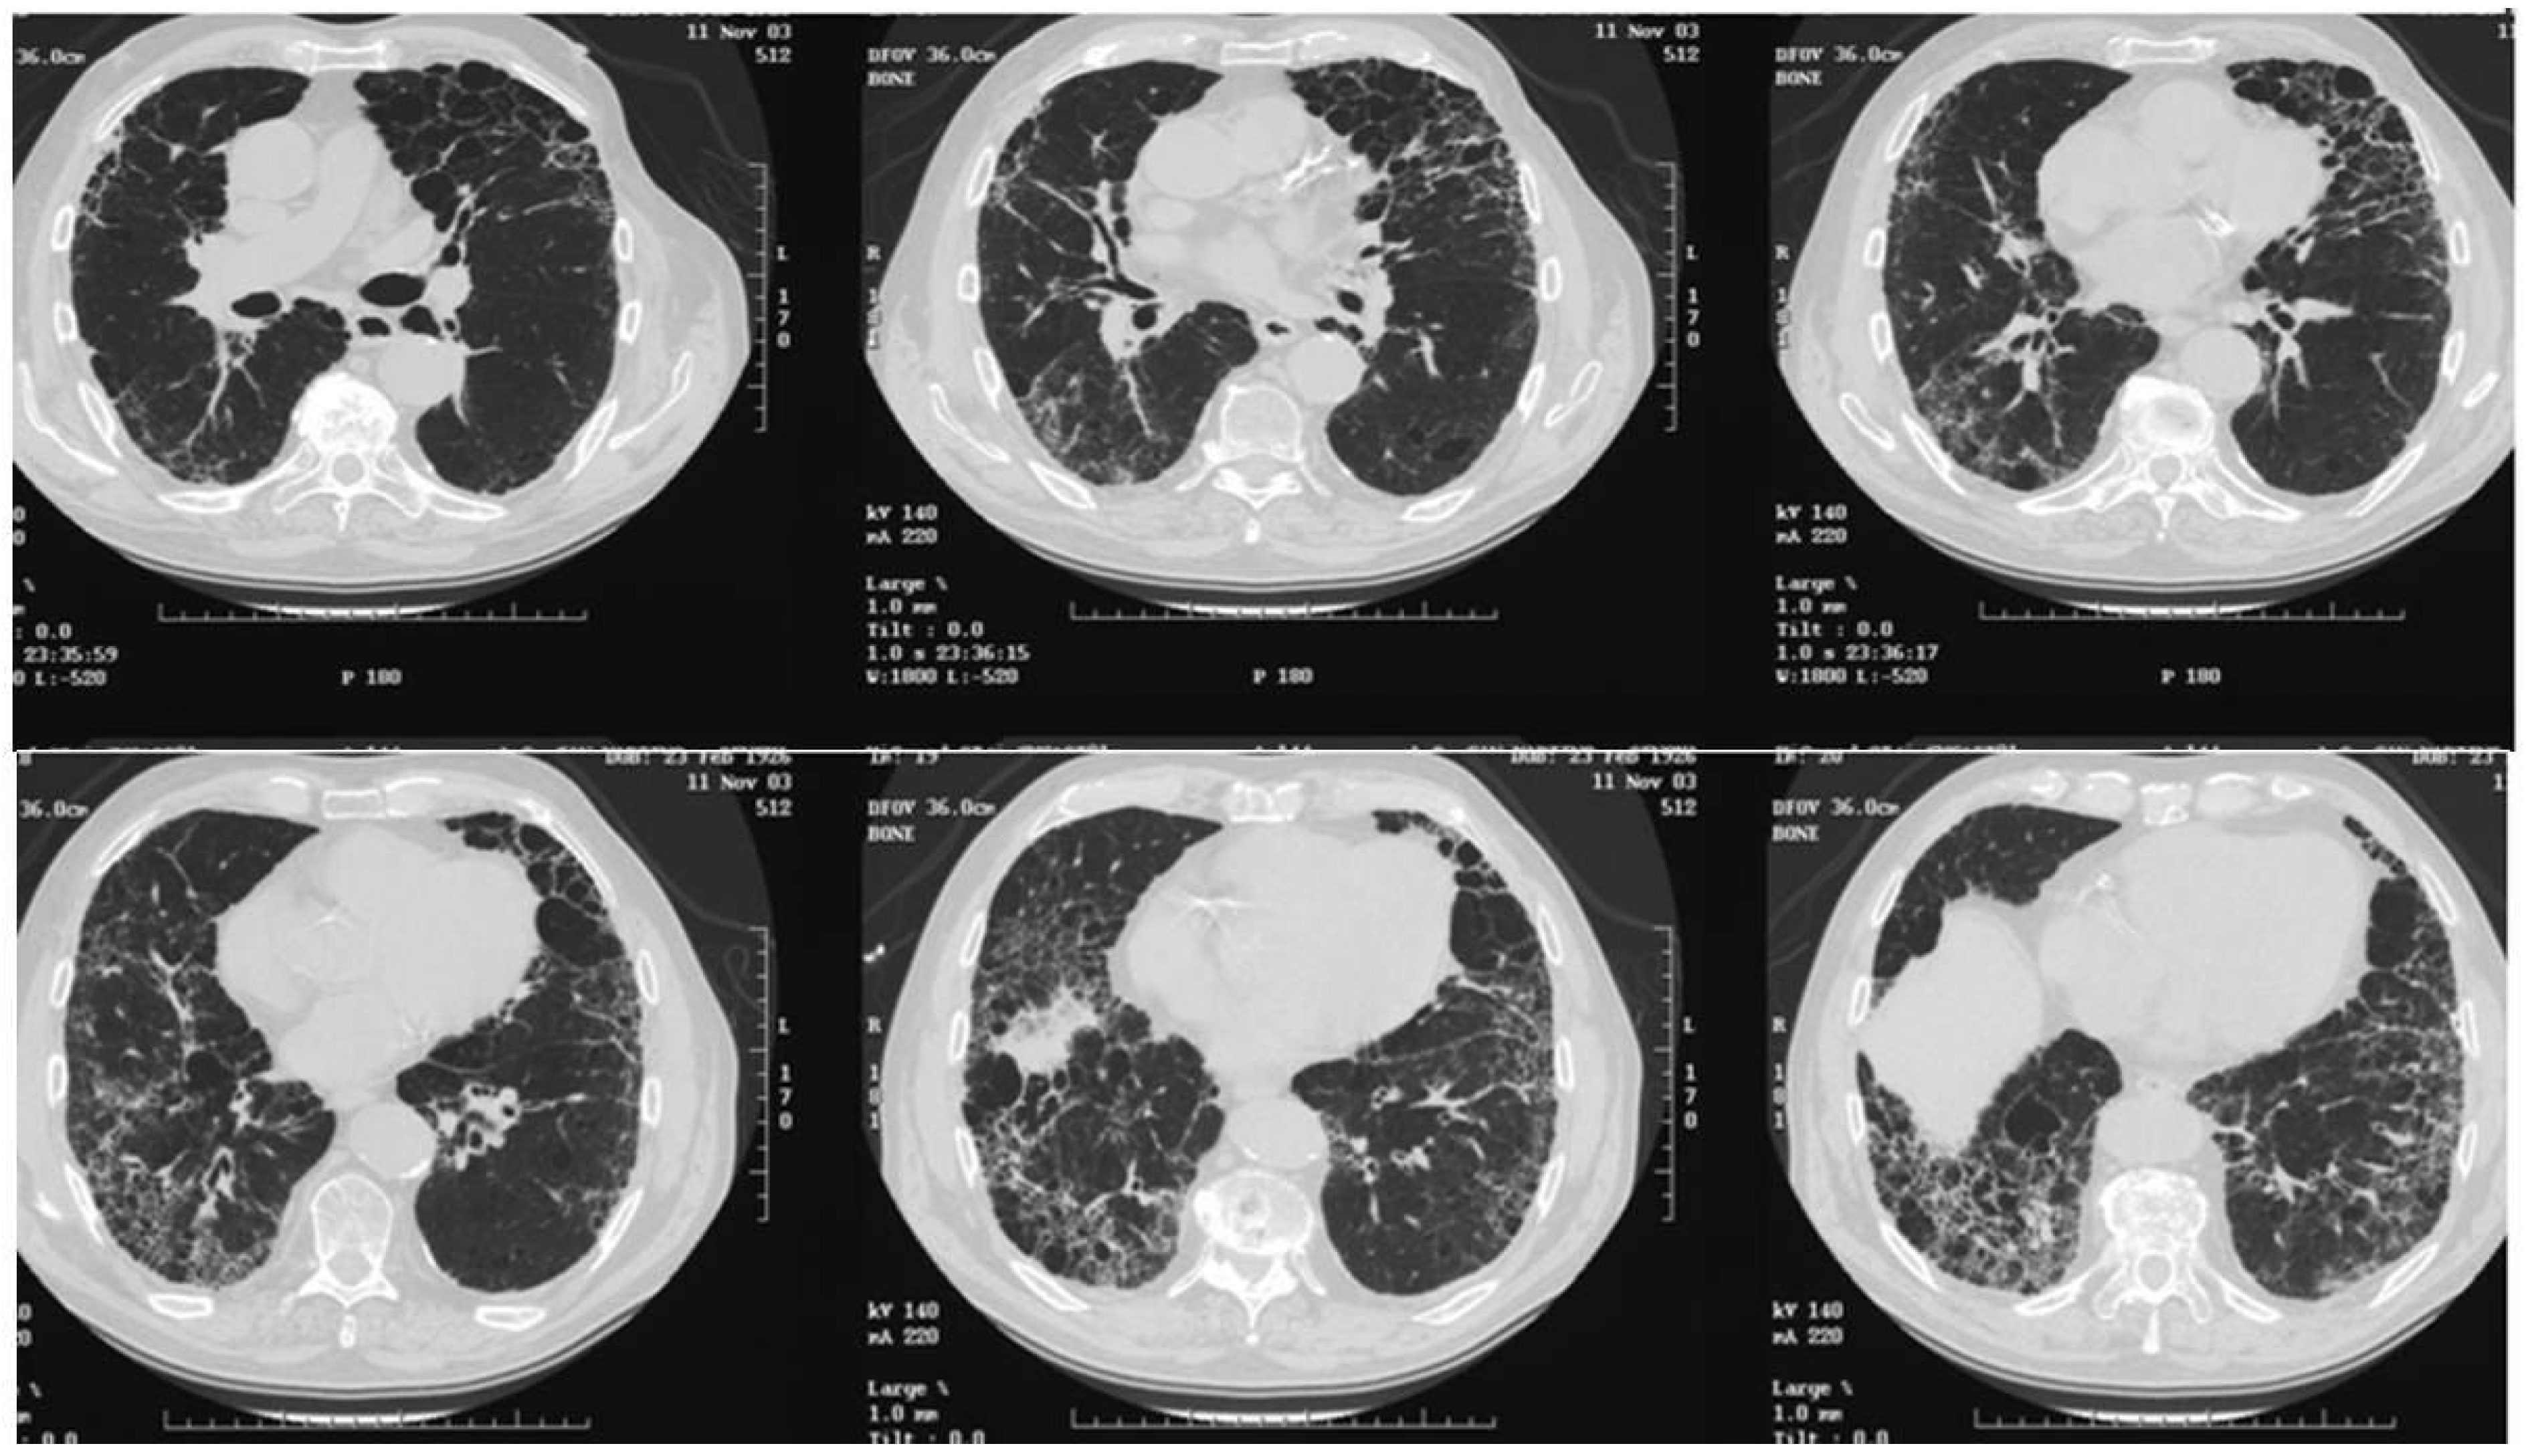

In 1995–2004 period 128 ILD patients were enrolled in Aosta region, Italy (126,000 inhabitants) (Table 5). According to the American Thoracic Society Criteria recommendation [22], the diagnosis was made on clinical, radiological, and histological data: 59 patients were diagnosed with IPF/UIP, 19 with NSIP, and the remaining 50 patients with sarcoidosis (n. 24), GPA (n. 16), and extrinsic allergic alveolitis (n. 10). All ILD diagnoses were confirmed by lung biopsy [23]. Interestingly, the registry was updated in 2018, including data from 2005 to 2018, and showed an increase in ILD incidence, also including ILD associated with GPA (Wegener’s) and hypersensitivity alveolitis (data not published). These data are at odds with other registries, in which the most frequent diseases were IPF and sarcoidosis. ILD incidence was 7 × 100,000 inhabitants. The accuracy of ILD diagnosis and registration was facilitated because patients were part of a region with a numerically reduced population of residents, they were referred to a single hospital center, and update courses on pulmonary fibrosis for general practitioners were implemented in close collaboration with hospital specialists. IPF high-resolution computed tomography (HRCT) scan and histopathological features are reported here (Figure 2 and Figure 3A,B).

Figure 2.

Series of chest HRCT images showing IPF characterized by reticular pattern and honeycombing associated with pulmonary emphysema.